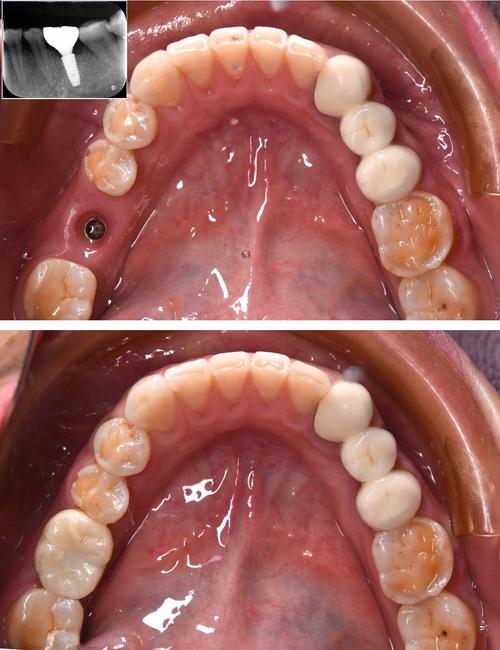

(图片来源网络,侵删)- 恢复期: 种植牙手术本身(尤其是单颗或多颗种植)通常需要一定的恢复时间(几天到几周不等),中秋节是法定假日,有连续几天休息,患者可以利用这段时间更好地休息、观察恢复情况,避免影响工作或学习。

(图片来源网络,侵删)- 种植牙是一个需要时间的生物过程(骨结合)。切勿为了在节日前完成而缩短必要的治疗周期(如骨结合时间不足就戴牙冠),否则可能导致种植失败,医生会根据你的口腔条件制定合理的治疗计划。